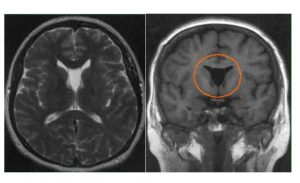

Основные методы инструментальной диагностики – исследование в формате МРТ или КТ. Нейровизуализация позволяет детально рассмотреть кисту, определить ее диаметр, морфологическое строение, точную локализацию, выявить характер влияния на окружающие ткани. Другие способы диагностики:

- Первичные — доброкачественные бессимптомные образования, появившиеся на ранних сроках формирования плода, рассасывающиеся самостоятельно, диагностируются у 60% новорожденных. Если женщина не доносила малыша, вероятность аномалии — 100%. Магнитно-резонансная томография «видит» новообразование с четкими гранями, однотипным содержимым;

На снимках визуализируются паренхиматозные кисты с гладкими закругленными границами и минимальным отражающим сигналом. Глиозные кисты составляет менее 1% от внутричерепных кистозных образований.

- МРТ или КТ позволяют локализовать размер и характер образований;